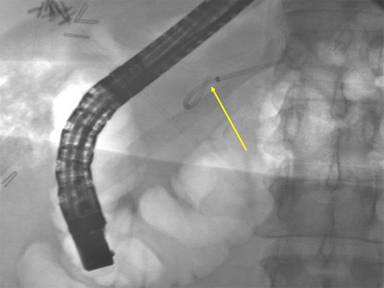

A 43-year-old female with history of morbid obesity (BMI equal to 45 kg/m2), dietary controlled diabetes mellitus, and depression presented to an outside institution complaining of a three-month history of persistent and worsening vague abdominal pain. She was found to have cholelithiasis by ultrasound as well as a dilated bile duct with abnormal liver enzymes. She underwent ERCP with failure to cannulate the bile duct. After several pancreatograms, a 3 cm long 5 Fr single pigtail pancreatic stent was placed to prevent post ERCP pancreatitis. The pancreatic duct stent was later found to have migrated into the neck of the pancreas, and she subsequently developed moderate pancreatitis after the procedure, requiring a nine day hospitalization. Two subsequent endoscopic attempts to remove the impacted stent were performed on days 5 and 26 after the first ERCP, but these were unsuccessful. The patient continued to have epigastric pain with amylase elevation and was also found to have radiographic evidence of acute cholecystitis. She underwent a reportedly difficult laparoscopic cholecystectomy, which was associated with a prolonged recovery time. The patient was then referred to our institution. A fourth attempt of endoscopic extraction was attempted but unsuccessful due to the inability to pass a guidewire past the embedded stent. This last ERCP revealed a proximally migrated stent into the ventral pancreatic duct at the level of the genu and proximal body of the pancreas (Figure 1). The main duct and side branches were moderately dilated. A computerized tomography scan showed the stent causing proximal pancreatic ductal dilation (Figure 2). The patient was then consulted for surgical management of the impacted stent.

Figure 1. ERCP image of the impacted retained pancreatic duct (arrow) stent within the genu and proximal body of the pancreas. |